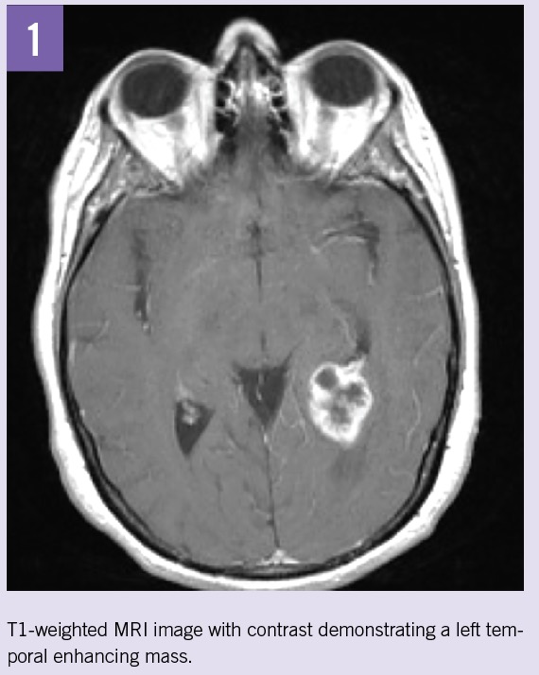

Sagittal T1-weighted MRI revealed a 3.7 × 3.0 × 3.3 cm, irregular, inhomogeneous mass in the posterior right frontal lobe with extensive surrounding vasogenic edema. Another mass in the left posteromedial temporal lobe straddling the left ventricular trigone was also identified, measuring 2.7 × 2.2 × 2.6 cm.